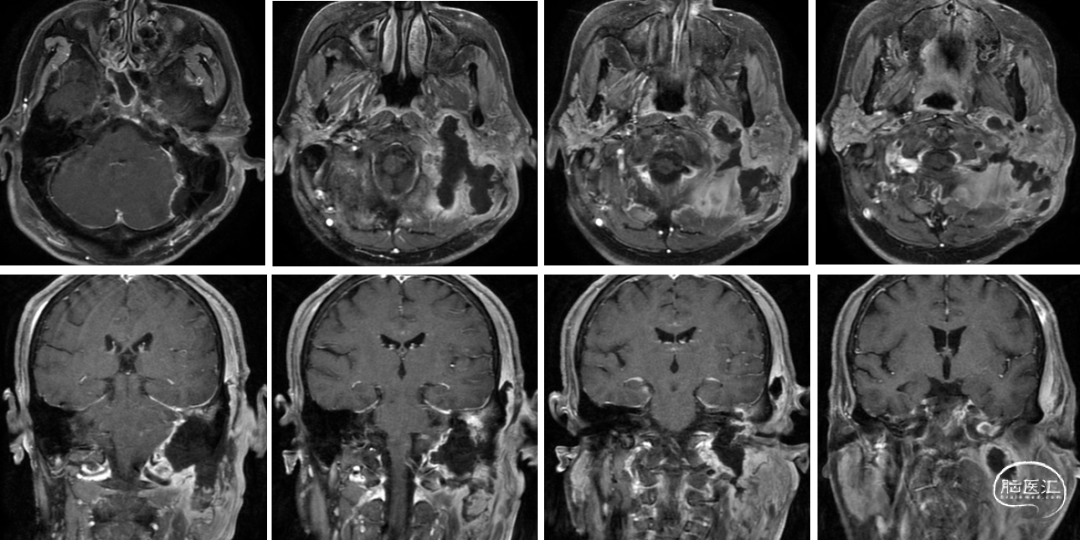

术前影像

术后影像

术后情况

患者术后恢复较好,面神经功能同术前,声音嘶哑、饮水呛咳症状同术前,无新发神经功能障碍。